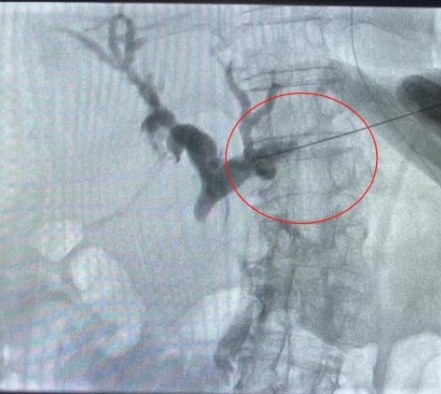

由于患者肝右葉占位巨大,完全遮擋右側(cè)穿刺路徑,左肝管為唯一穿刺路徑。介入科彭鵬醫(yī)生與重癥醫(yī)學(xué)科討論后,征得患者家屬同意后,擬行左側(cè)經(jīng)皮肝內(nèi)膽管穿刺引流術(shù)。術(shù)中一針便成功進(jìn)入膽道系統(tǒng),導(dǎo)絲引流管放置順利,造影顯示膽道系統(tǒng)顯影滿意,側(cè)孔位置可,引流順暢,37分鐘便結(jié)束了手術(shù),術(shù)后順利轉(zhuǎn)入普外科護(hù)理治療。這例手術(shù)的成功開(kāi)展,刷新了該院介入團(tuán)隊(duì)高齡患者手術(shù)的新記錄!

經(jīng)皮肝內(nèi)膽管穿刺引流術(shù)是在醫(yī)學(xué)影像的引導(dǎo)下,利用穿刺針經(jīng)皮穿入肝內(nèi)膽管,注入對(duì)比劑,使肝內(nèi)外膽管迅速顯影后,置管引流以緩解梗阻癥狀。對(duì)于惡性梗阻性黃疸患者,通過(guò)該方式可降低血清膽紅素,有助于恢復(fù)肝腎功能,提高其生存質(zhì)量,延長(zhǎng)生存期,部分患者還可獲得進(jìn)一步治療的機(jī)會(huì)。對(duì)于良性梗阻性黃疸患者,除有利于迅速緩解黃疸和感染等癥狀外,還可為后續(xù)治療提供通道。